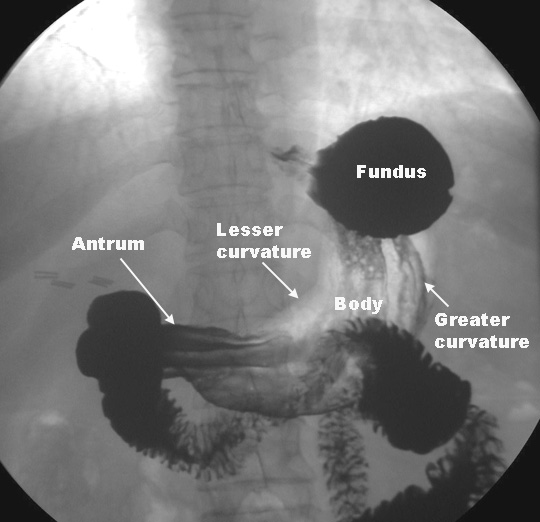

Gastric cardia radiology. Diagnostic centers of america dca is a leading diagnostic imaging facility offering a full array of imaging services in palm beach county florida. We have five state of the art radiology imaging centers in boca raton boynton beach delray beach and wellington florida. The gastric cardia is characterized on barium stud ies by three or four stellate folds that radiate to a central point at the gastro esophageal junction also known as the cardiac rosette fig 2 12. Variations and benign influences may closely resemble the more dangerous lesion.

Cain jc jordan gl jr comfort mw gray hk. J am med assoc. The gas tric fundus is dened as the portion of the stomach craniad to the gastric car dia. Commonly accompanying this are abnormally dilated short gastric veins which pass from the splenic vein to encircle the gastric fundus and form gastric fundal varices.